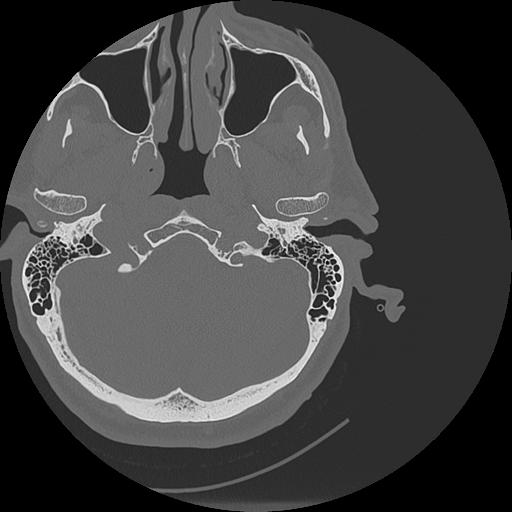

7 HUESO,,Vol,0.5,HUESO,,